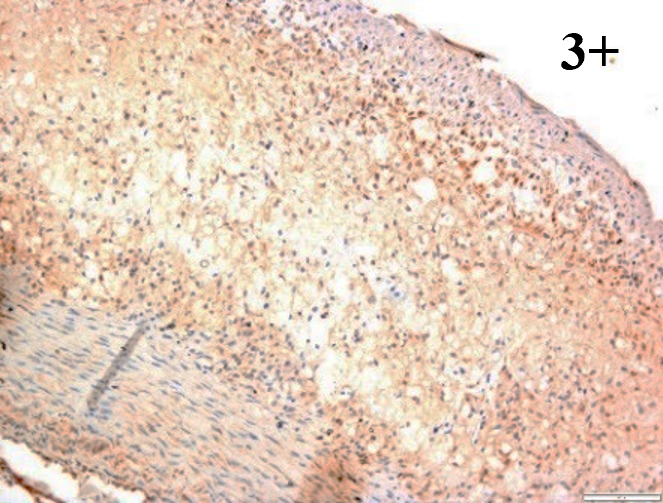

According to the percentage endothelial staining of cells, semi-quantitative

scores were applied. Score: 0 (negative); 1+ (1–10% positive cells); 2+

(11–25% positive cells) and 3+ (